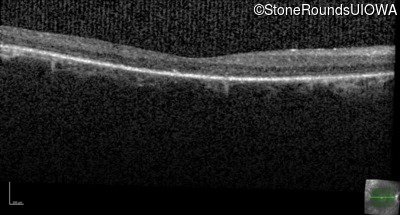

Age at visit: 59 years

OD OS